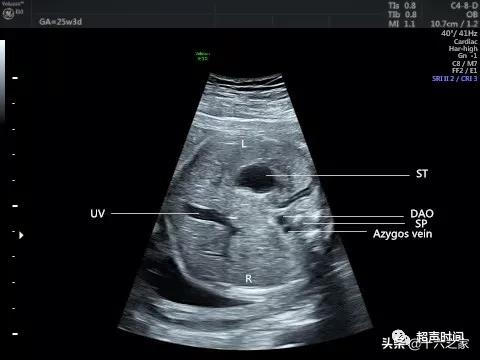

图 1 和视频 1 臀位胎儿腹部横切面示腹主动脉位于脊柱左前方 , 未见下腔静脉 , 扩张的奇静脉位于腹主动脉右后方 , 胃泡位于左侧腹腔 , 脐静脉弓背朝向胃 。 SP :脊柱;DAO :降主动脉;Azygos vein :奇静脉;ST :胃泡;UV :脐静脉